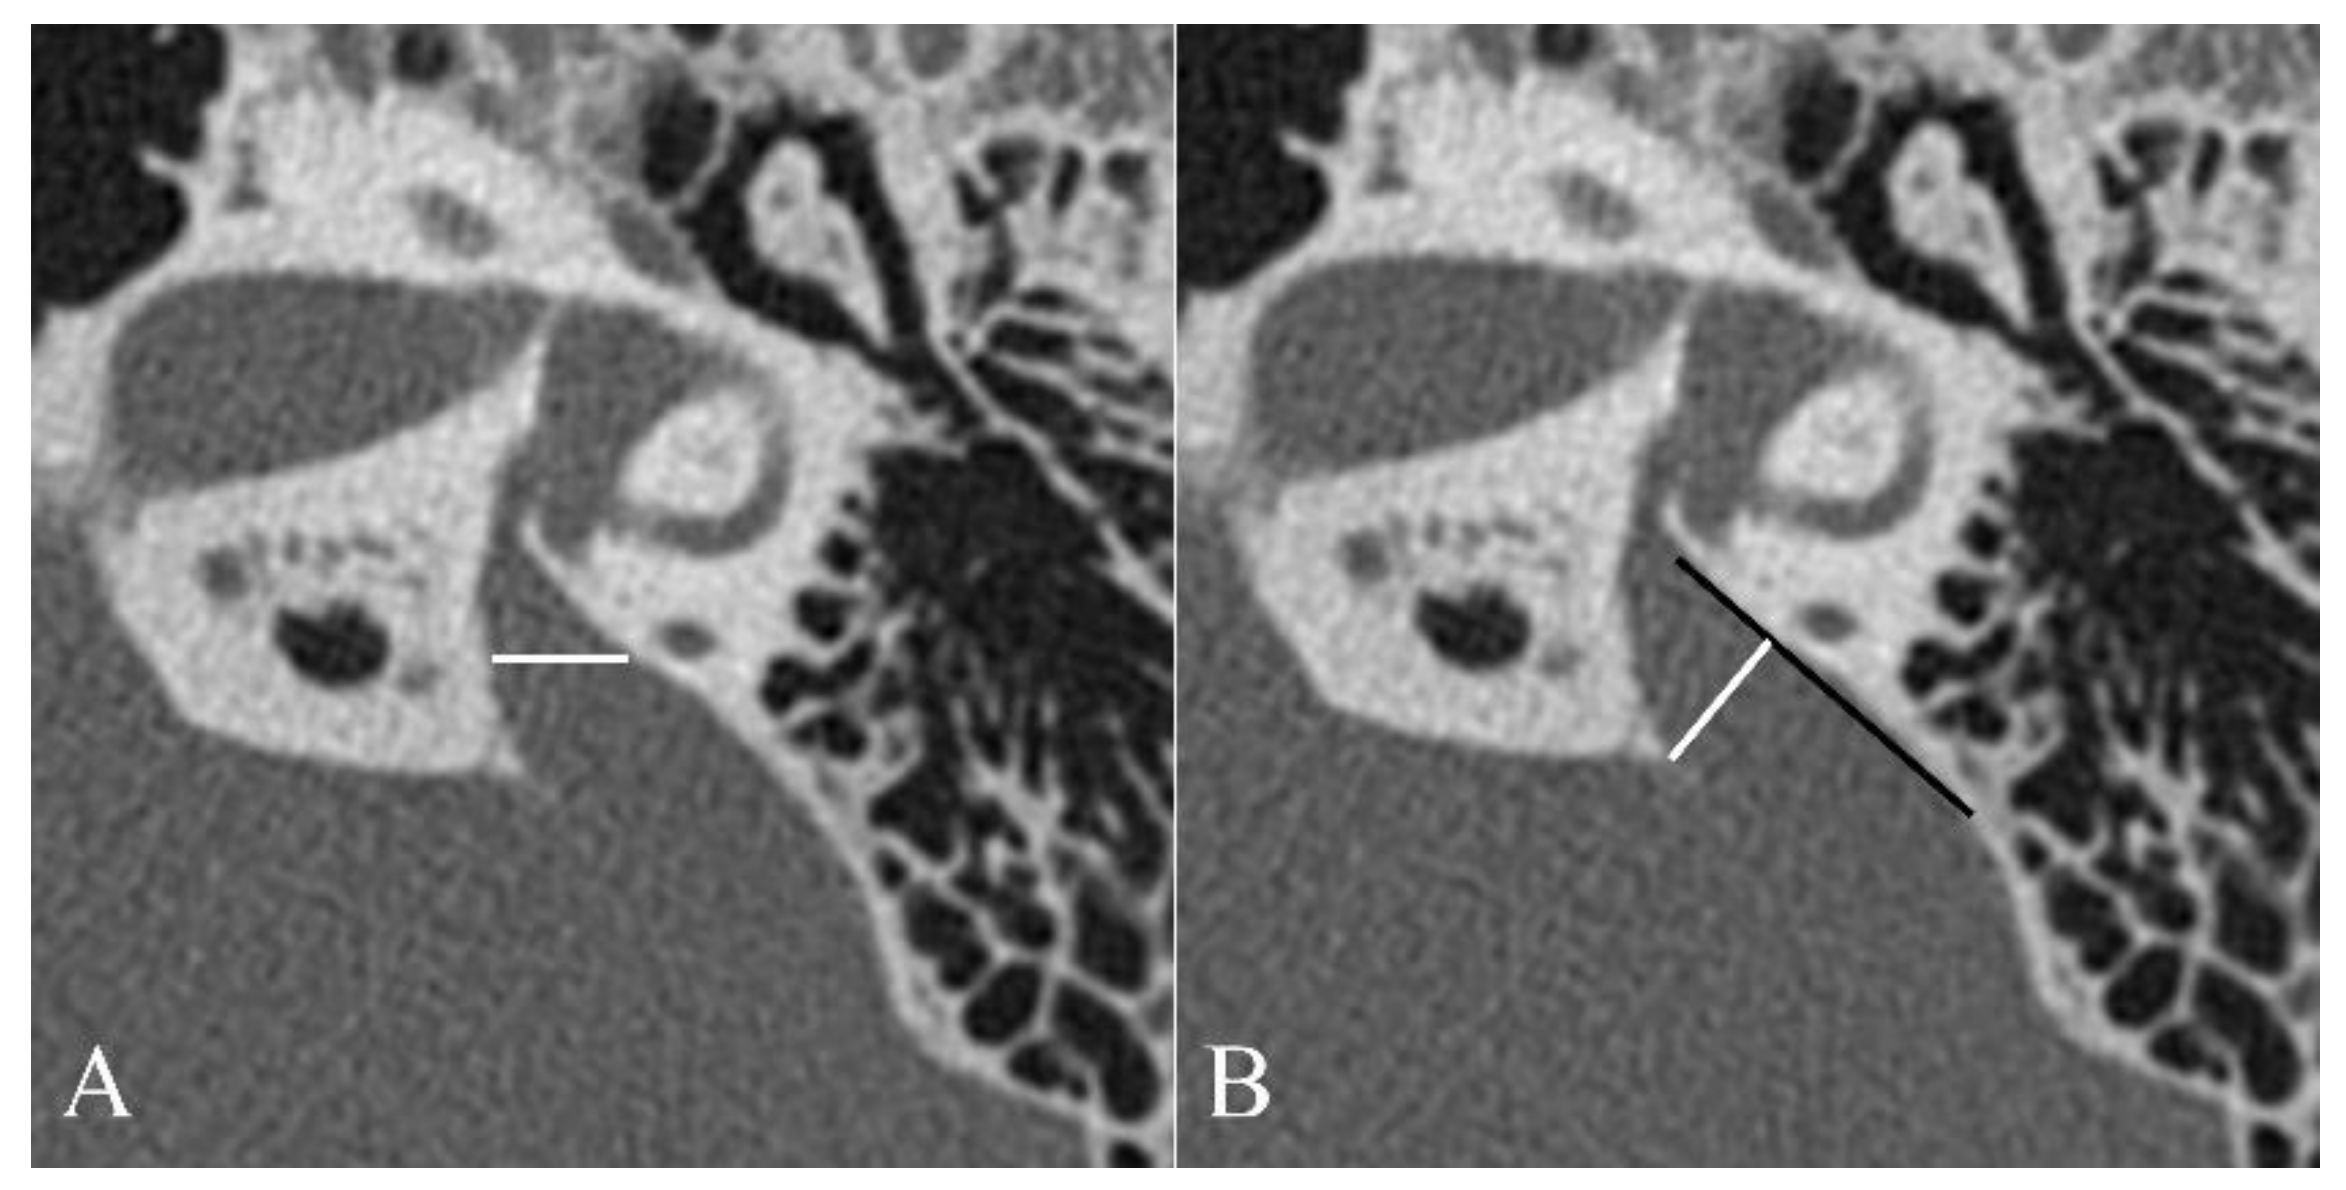

| 2 | VA with a diameter of >1.5 mm at the midpoint |